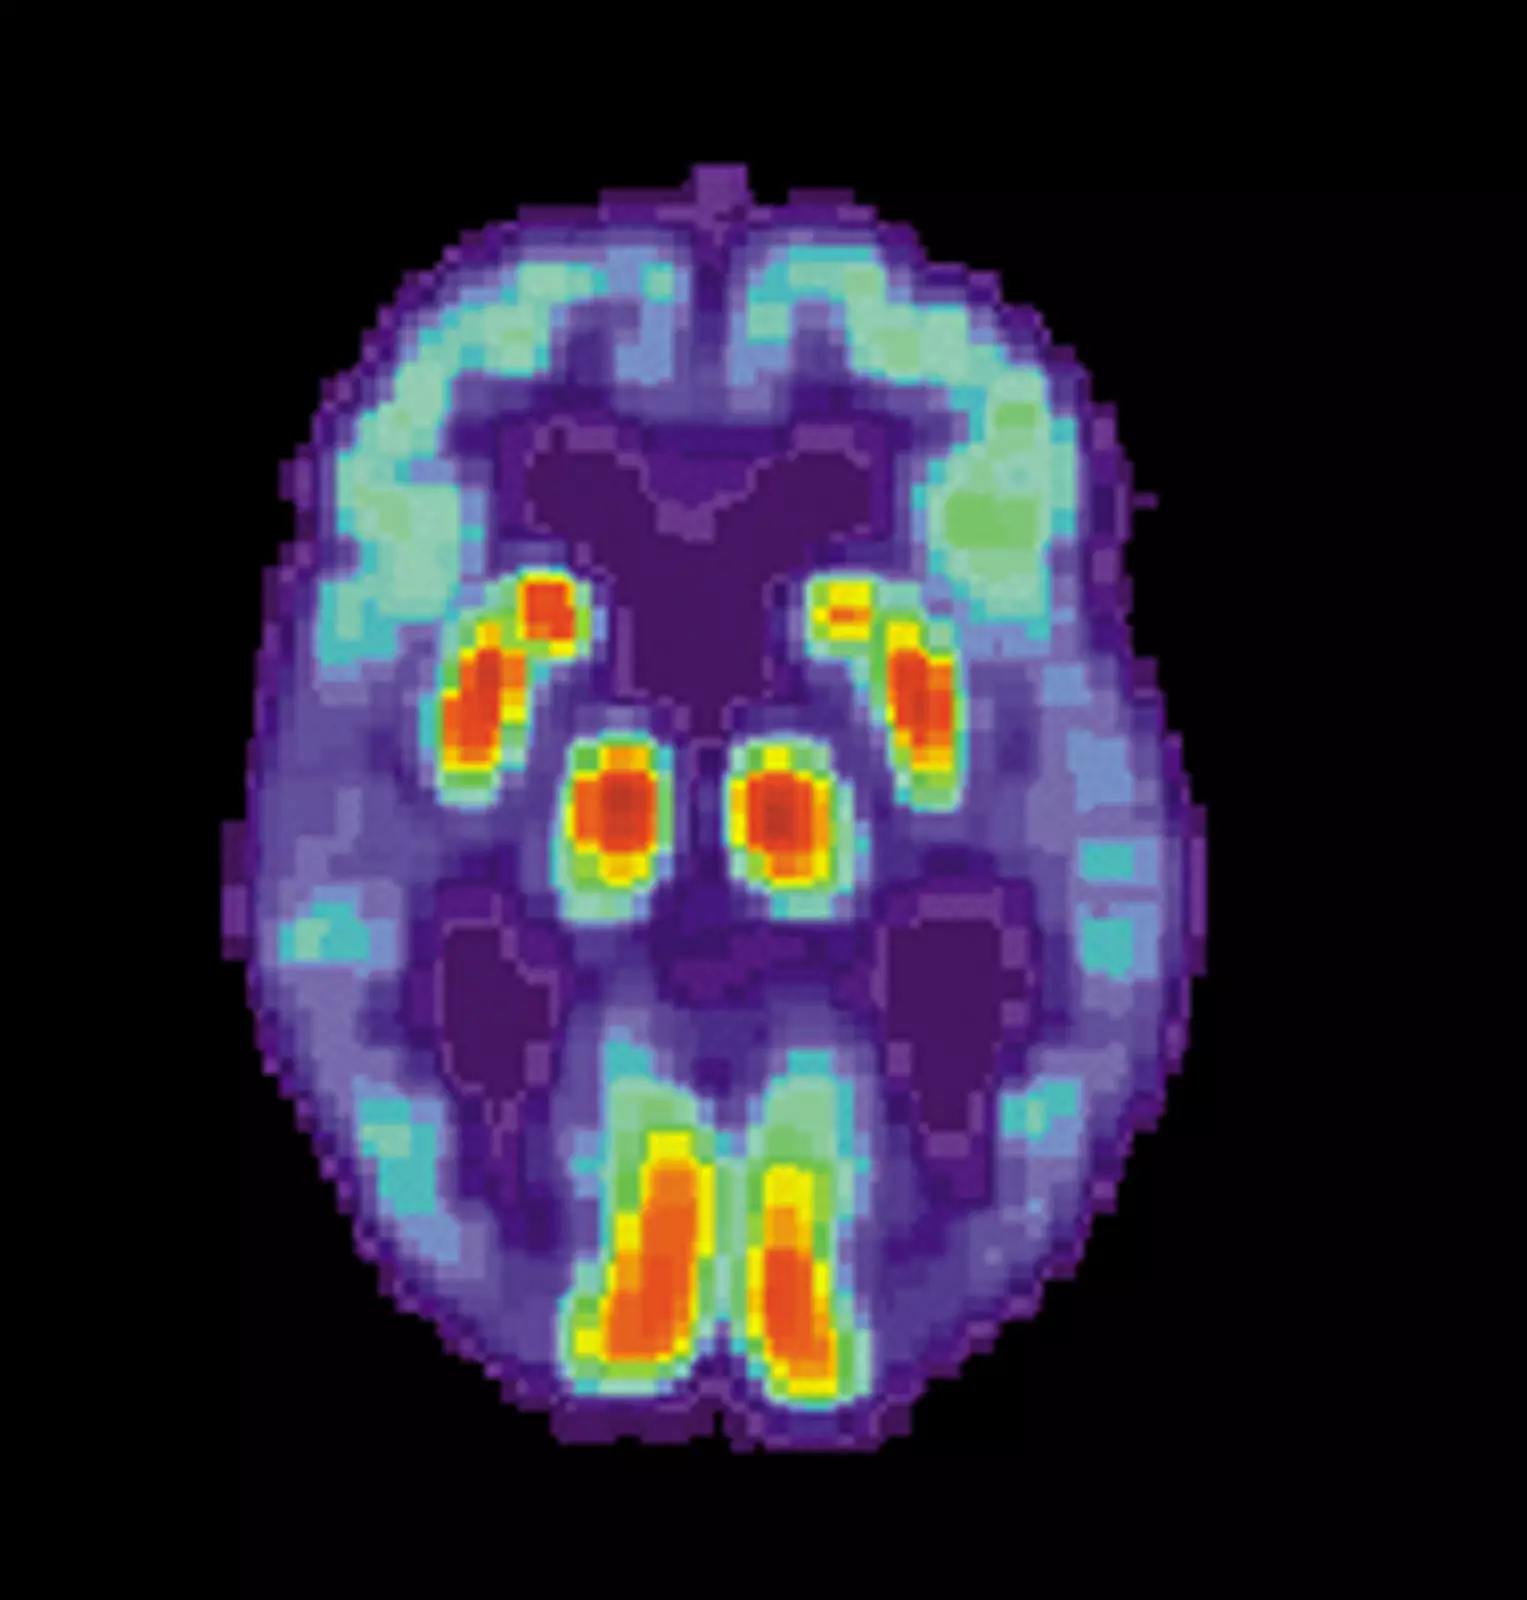

Нужный алгоритм изначально был разработан для классификации раковых опухолей, однако учёные адаптировали его для МРТ, разделив мозг на 115 областей и выделив 660 различных характеристик, таких как размер, форма и текстура, для оценки каждой области. Затем они обучили алгоритм определять, где изменения этих характеристик могут точно предсказать наличие болезни Альцгеймера.

Учёные обнаружили, что в 98% случаев одна только система машинного обучения на основе МРТ смогла точно показать, есть у пациента болезнь Альцгеймера или нет. Система также смогла различить раннюю и позднюю стадии болезни с довольно высокой точностью у 79% пациентов.

Более того, новая методика позволила обнаружить изменения в областях мозга, ранее не связанных с болезнью Альцгеймера, включая мозжечок (часть мозга, которая координирует и регулирует физическую активность) и вентральный промежуточный мозг (связанный с органами чувств, зрением и слухом).